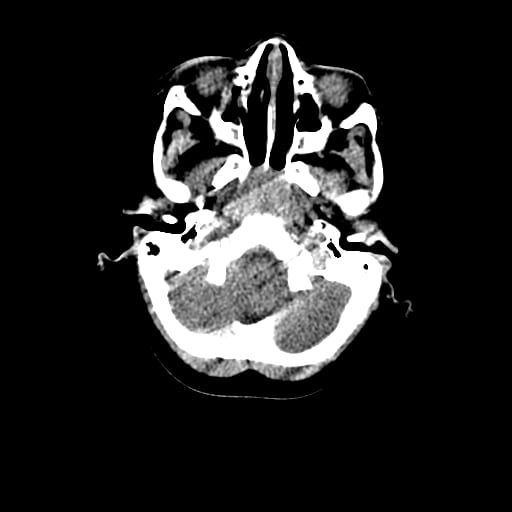

Age: 1

Sex: Male

Indication: Fall